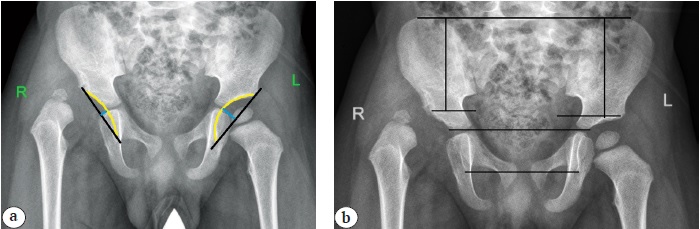

All patients underwent reconstructive surgery through the anterolateral approach. After performing intra-articular manipulations, osteotomy of the femur with excision of the bone autograft, and additional shortening of the femur in group I, a subperiosteal approach and osteotomy of the ilium body were performed. Thereafter, the acetabular fragment was rotated outward and anteriorly using a tenaculum. In the position of the achieved correction, an autograft from the femur was placed in the diastasis between the fragments of the ilium and fixed with 3-4 Kirschner wires (Fig. 2).

Fig. 2. X-rays of hip joints of patient born in 2018 with hip dysplasia IHDI type IV in an anterior-posterior projection: a — before surgery; b — after surgical treatment using Salter’s osteotomy